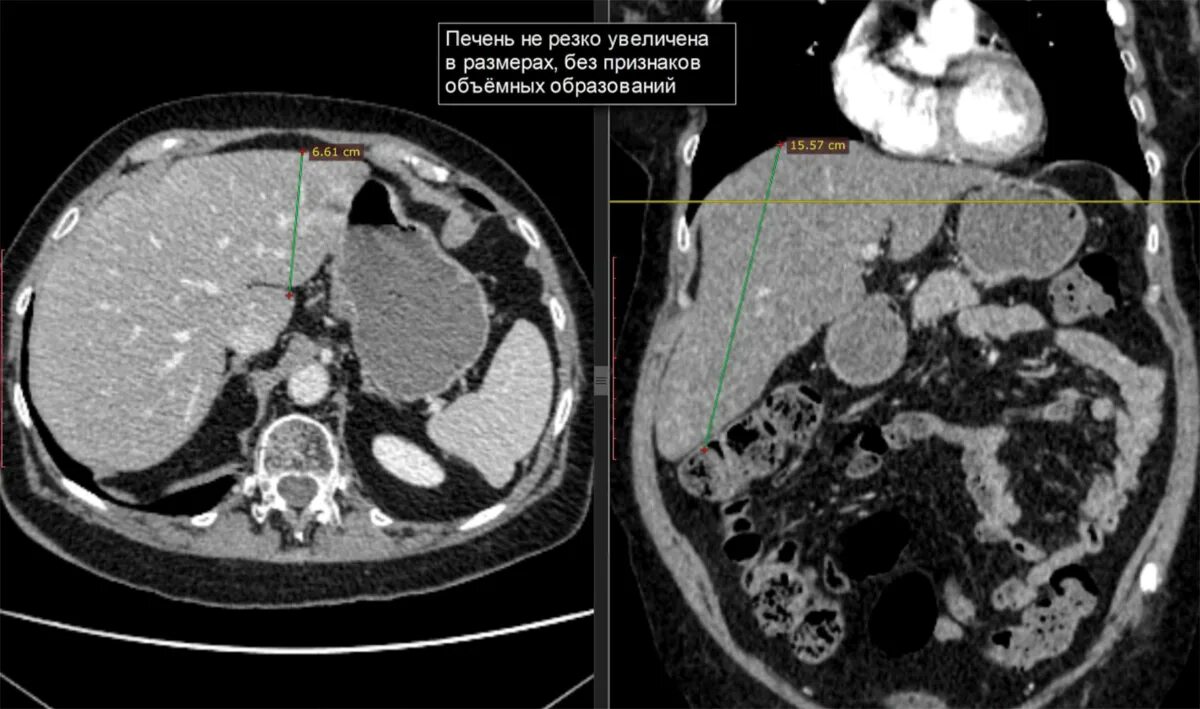

Диффузные изменения печени кт